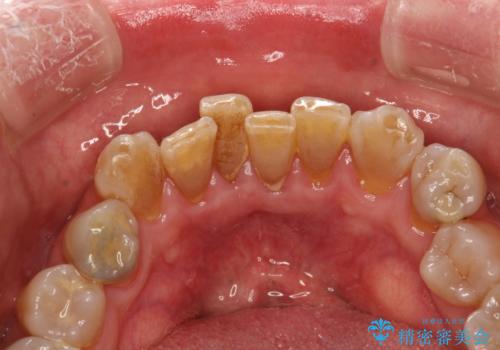

歯周外科前のクリーニング

- 歯周外科を行う前に、しっかりと汚れを除去し外科治療がスムーズに行えるようにとのことでPMTC30分コースを行いました。

治療前のクリーニングを行うことで、より処置がスムーズに行えること・処置後の腫れや感染予防にもなります。また、外科治療をおこなった後は、傷口の治りを待つため、しっかりとブラッシングできない状態になります。そのため処置前に、なるべくお口の中を清潔にしておくことが大切です。

親知らずの抜歯やインプラント治療の前などに、PMTC(専門器具による歯の機械的な清掃)を行うことをおすすめします。